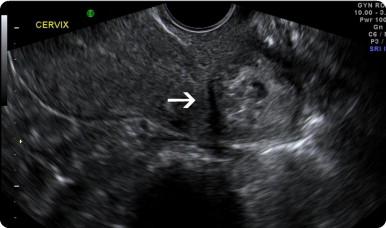

患者,女,年龄36岁,通过宫内受精而怀孕,因被检查出宫颈异位妊娠而被转至本院。当地医院在该患者妊娠6周零6天时查出异位妊娠,在其妊娠7周时给予单剂甲氨蝶呤50 mg/m2肌内注射,妊娠9周时再次给药。然而这2次治疗均未能解决异位妊娠。该患者在妊娠11周零1天时来到本院接受进一步治疗。当时,她的人绒毛膜促性腺激素(hCG)水平为26,861 IU/L。该患者否认任何阴道出血或疼痛。 结论 超声影像显示,异位妊娠位于宫颈基质后部(见图1)。值得注意的是,胎儿颈背部皱褶厚度为2.3 mm。该患者在入院当天接受了子宫动脉栓塞术;次日,在手术室对进展期异位妊娠进行根除治疗。通过阴道窥镜发现,宫颈后方有1处缺损伴胎膜脱垂(见图2)。吸出8 ml羊水,送往实验室进行细胞学分析。然后将1枚细针插入胎儿胸腔,向胎心内注射氯化钾以确保胎儿死亡。在胎儿心搏停止后将细针从胎儿体内撤出,向羊膜腔内缓慢注入甲氨蝶呤80 mg。整个手术过程在动态超声引导下进行。

图2. 宫颈后方可见缺损伴胎膜脱垂(黑箭头)。